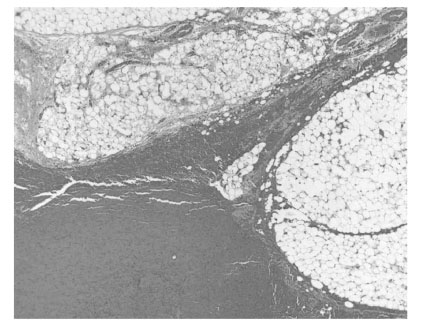

Fig. 2B). After separation of the fat mass from the cord structure, the hernia sac was ligated at the level of the internal ring and excised. A hemorrhagic PPF measuring about 3.0 × 2.0 × 1.5 cm. was also excised at the level of the internal ring. The wound was closed in layers and protected by collodion. Pathology showed hemorrhage of lipoma (

Fig. 3).

Fig. 3Microscopic findings showing hemorrhage of lipoma (H & E).